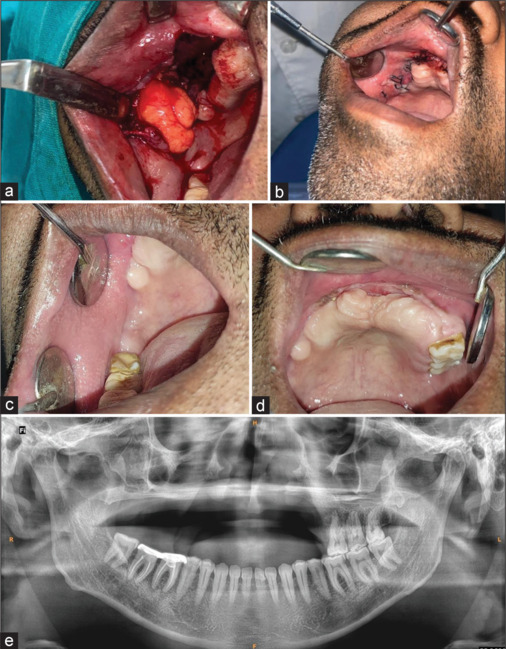

上颌放线菌性骨髓炎是一种罕见的并发症,特别是在糖尿病患者后登革热感染。由以色列放线菌引起的放线菌病通常发生在免疫功能低下的宿主中,登革热引起的免疫失调和糖尿病是其发病机制的一部分。本病例报告描述一名42岁男性糖尿病患者,在登革后20天表现为口中腔相通,上颌后牙松动,持续脓流。影像学显示骨质侵蚀,组织病理学证实放线菌病。患者接受了部分上颌切除和抗生素治疗,在6个月内完全康复。这一病例强调了早期诊断和量身定制治疗在易受感染人群中罕见细菌感染的重要性。

Actinomycotic osteomyelitis in the maxilla is a rare complication, particularly in diabetic patients following dengue infection. Actinomycosis, caused by Actinomyces israelii, typically arises in immunocompromised hosts, with dengue-induced immune dysregulation and diabetes contributing to its pathogenesis. This case report describes a 42-year-old diabetic male presenting with oroantral communication, loose posterior maxillary teeth, and persistent pus discharge 20 days postdengue. Imaging revealed bone erosion, and histopathology confirmed actinomycosis. The patient underwent partial maxillectomy with antibiotic therapy, leading to full recovery within 6 months. This case emphasizes the importance of early diagnosis and tailored treatment in managing rare bacterial infections in vulnerable populations.